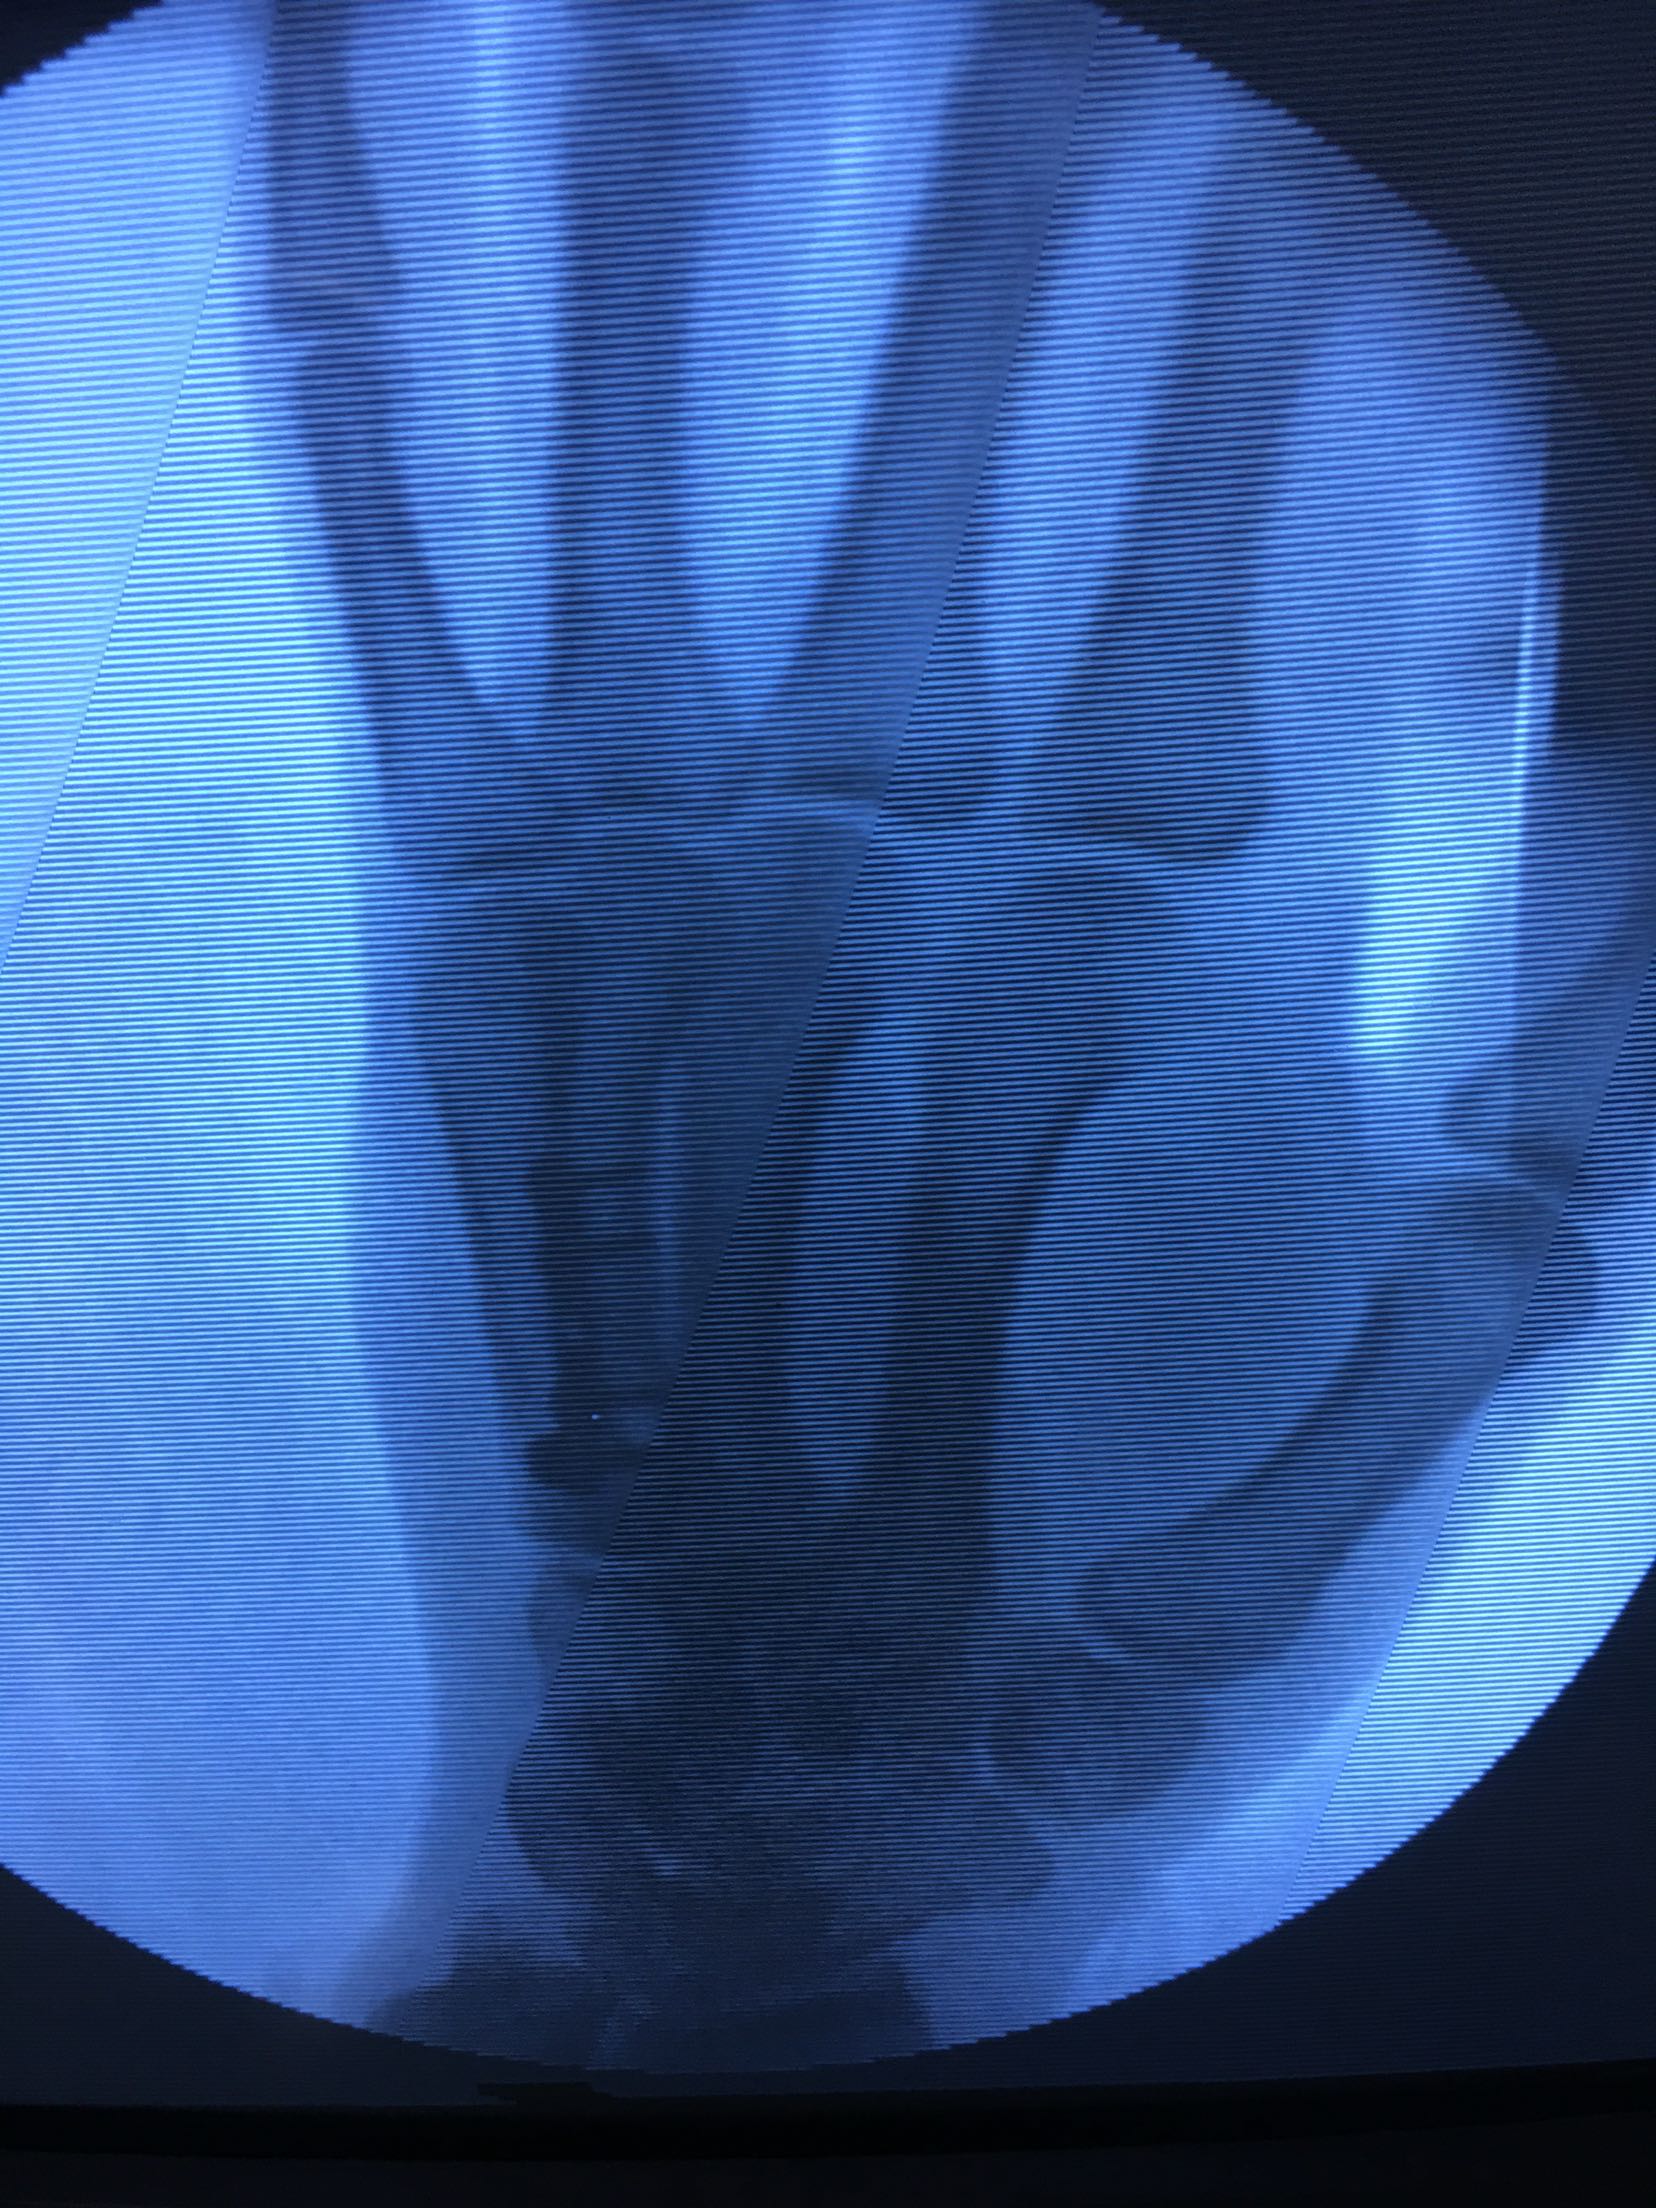

患者,男,52岁,摔伤后右手肿痛,活动受限4小时入院。

右手掌肿胀明显,皮色皮温正常,局部压痛,纵叩痛阳性,可及骨擦感,第四掌指关节活动受限,末梢血运感觉正常。

完善检查,在臂丛麻醉下行切复内固定术,术后抗炎,消肿止痛处理。